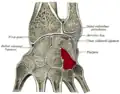

Cross section of wrist (thumb on left). Hamate shown in red.

Cross section of wrist (thumb on left). Hamate shown in red. -